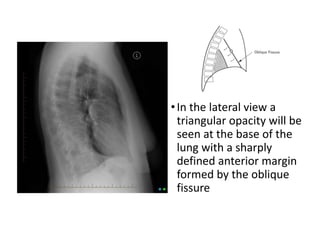

•In the lateral view a

triangular opacity will be

seen at the base of the

lung with a sharply

defined anterior margin

formed by the oblique

fissure